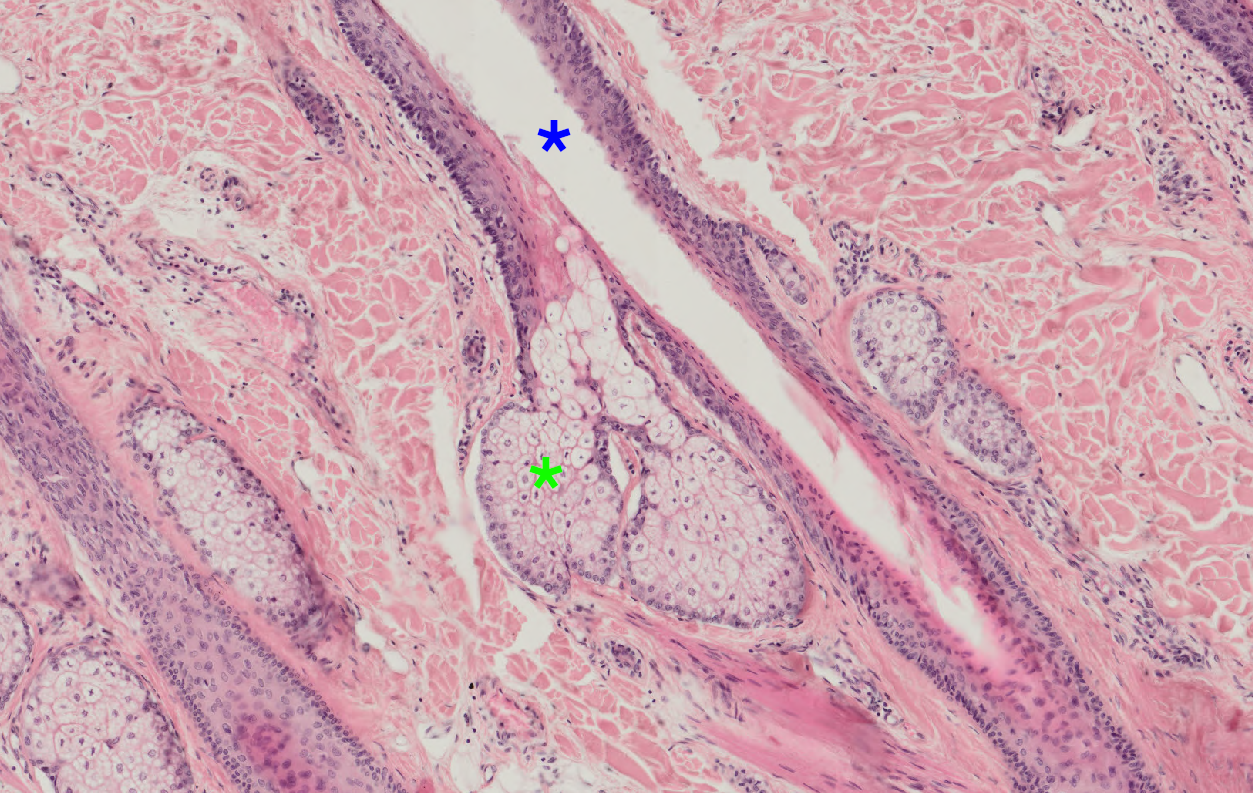

12 Na snímku je detail tenkého typu kůže (hematoxylin eosin). Zelenou hvězdičkou je označená mazová žláza. Co je označeno modrou hvězdičkou?

Kuze mazova.png

Vývod mazové žlázy

Vývod potní žlázy

Vlasový folikul

Artefakt